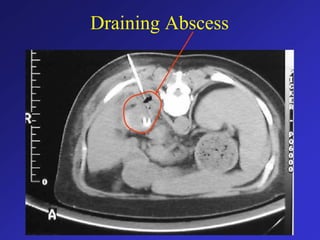

• Catheters to drain abscesses

Draining Abscess